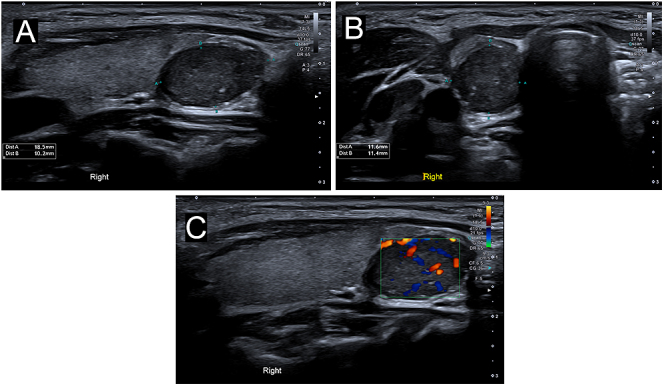

Abstract Image